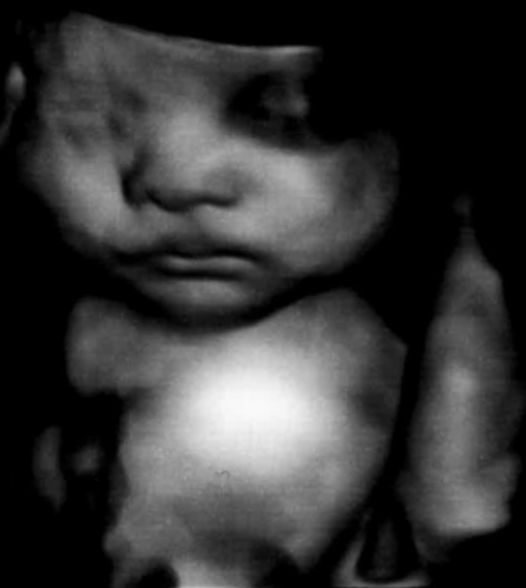

助産師による4Dエコーのご案内

赤ちゃんのかわいらしい様子をゆっくり見ることができます

ご家族の方も同席し、お話を聞いていただくこともできます

対象者

妊娠14週以降の妊婦さんとご家族

※お子さんも一緒にエコーを見ることができます

料金

2,000円(税込)

ご予約・問い合わせ:産婦人科外来

TEL0143-24-1331

【電話受付】平日 13:00~15:00

【予約枠】火~金曜日 12:00~14:30(最終受付14:00)

1枠30分の完全予約制となります